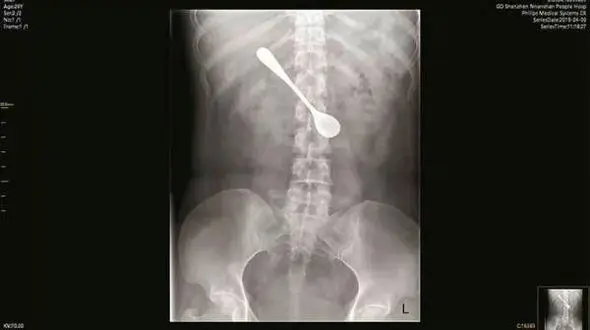

حوادث رکنا: قاشق 13 سانتی متری از شکم یک زن چینی خارج شد.